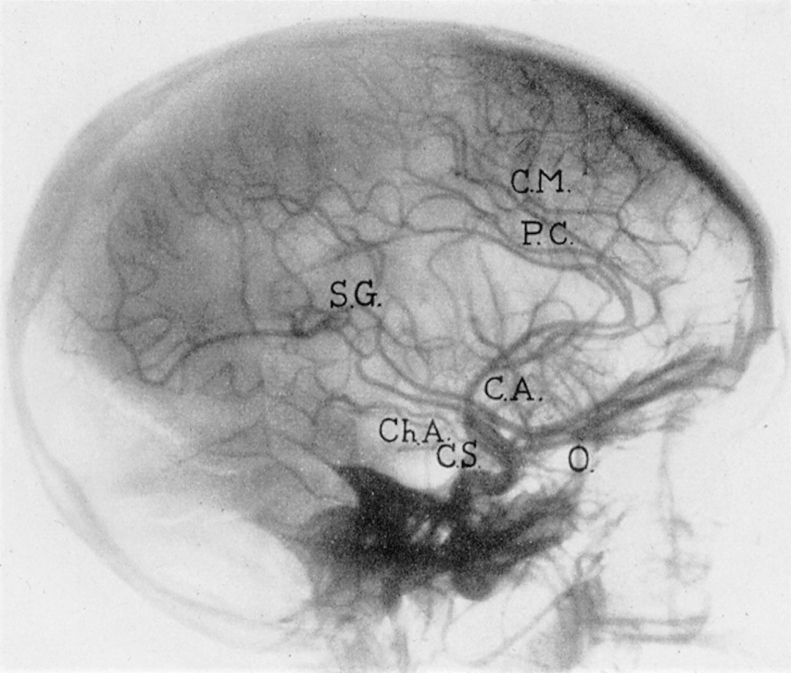

Die wässrige Suspension von 25% kolloidalem Thoriumdioxid (ThO2) erzeugt aufgrund der hohen Ordnungszahl (Z = 90) und des hohen Absorptions-Wirkungsquerschnitts eine große Opazität für Röntgenstrahlen und damit sehr kontrastreiche Bilder. Das Kontrastmittel zeigte im Vergleich zu den damals verfügbaren Alternativen praktisch keine unmittelbaren Nebenwirkungen. Thorotrast erwies sich somit als ideales, für die Zeit alternativloses Röntgenkontrastmittel für Darstellungen von Hohlräumen und engen Gefäßen. Es konnte sowohl intravenös als auch intraarteriell appliziert werden. Die Applikation von Thorotrast erfolgte bei etwa 70% der Patienten und Patientinnen als Injektion in die Halsschlagader und bei 30% in die Arterien der Beine oder der Arme. Nach der Injektion von durchschnittlich 25 ml Thorotrast, das 5 g Thorium mit einer Aktivität von 0,5 μCi bzw. 18,5 kBq 232-Th und additiv weiterer Zerfallsprodukte enthielt [13], in die Arteria carotis konnten besonders kontrastreiche Bilder des Gehirns (arterielle Enzephalographie) gewonnen werden.(Abb. 2) Bei der Aortographie der Extremitäten wurden herkömmlich 20 ml in die entsprechenden Gefäße injiziert.

Abbildung 2.

Normale zerebrale Angiographie mit Thorotrast.